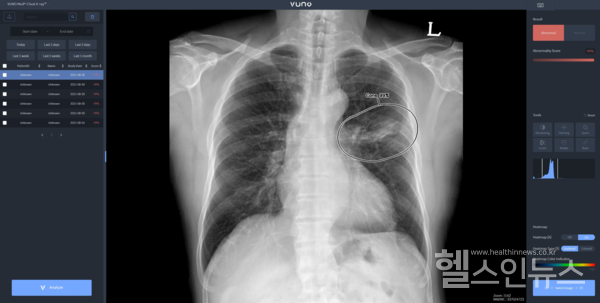

우즈베키스탄 군 병원에 도입된 솔루션은 뷰노의 AI 기반 상지 엑스레이 판독 보조 솔루션 ‘뷰노메드 익스트리미티 엑스레이(VUNO Med-Extremity X-ray)’와 이동형 엑스레이 장비에 AI 기반 흉부 엑스레이 판독 보조 솔루션 ‘뷰노메드 체스트 엑스레이(VUNO Med-Chest X-ray)’를 탑재한 패키지 제품이다.

두 제품은 모두 뷰노가 과학기술정보통신부 및 정보통신산업진흥원(이하 NIPA)이 추진하는 ‘군 의료영상 데이터 기반 인공지능 판독 시스템 고도화 및 실증 사업(이하 군 의료 사업)’의 일환으로 개발된 제품이다. 격오지를 중심으로 현장 의료서비스가 가능하도록 설계돼 의료 인프라가 낙후한 지역에서도 진단 편차를 줄이고 의료진의 진단을 효과적으로 도울 수 있다.